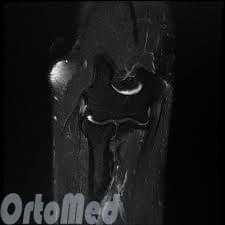

Магнитно-резонансная томография (МРТ) четко показывает мягкие ткани: измененные сухожилия, воспаленные участки.